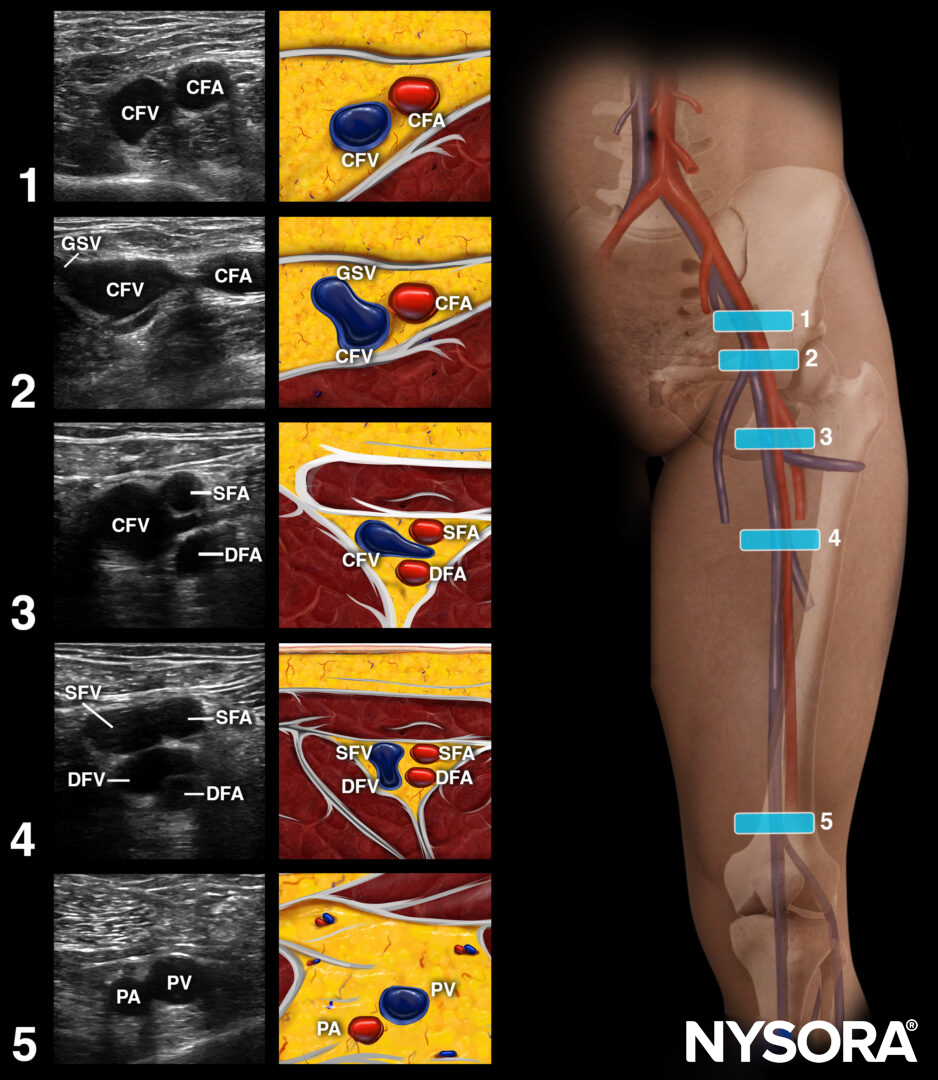

Approach for DVT scanning: Apply pressure at the following 5 points to compress the veins.